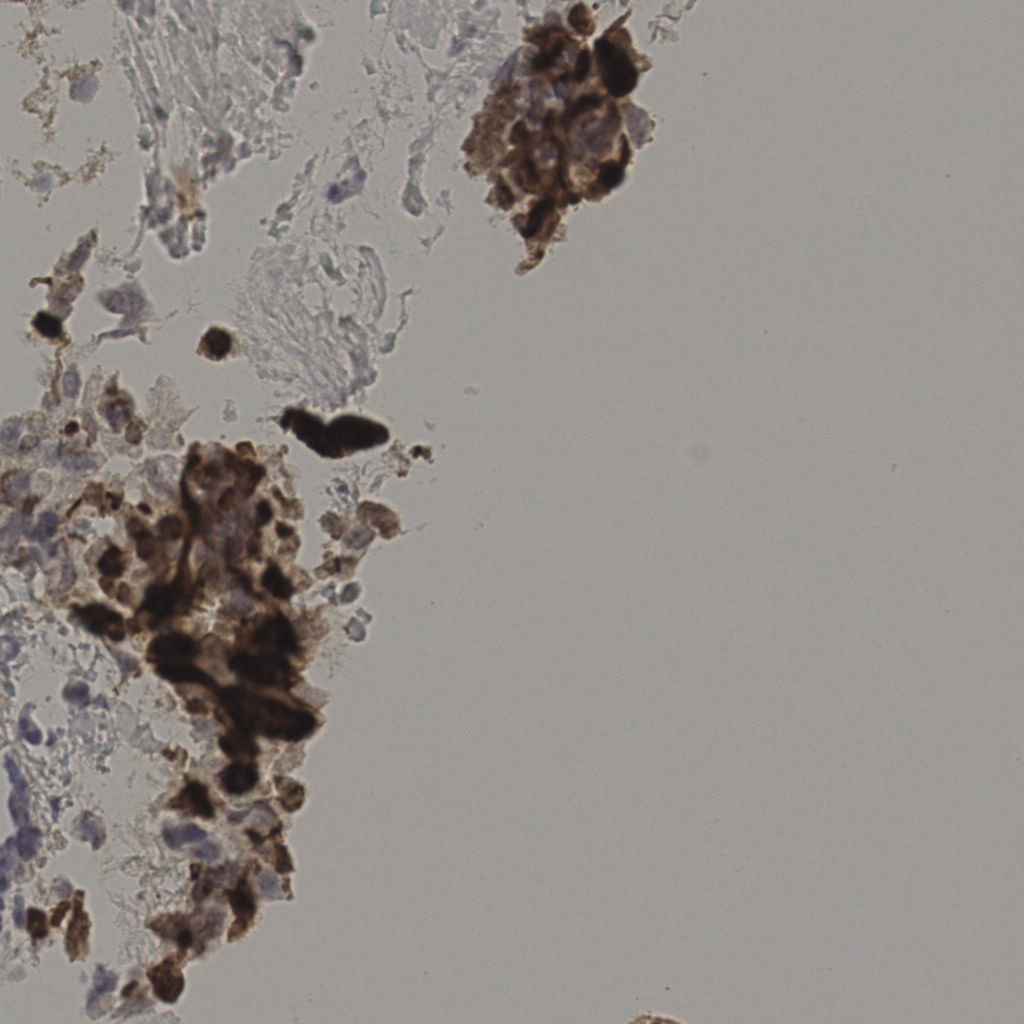

17.75%

Ki67 指数

阴 7986 阳 1723